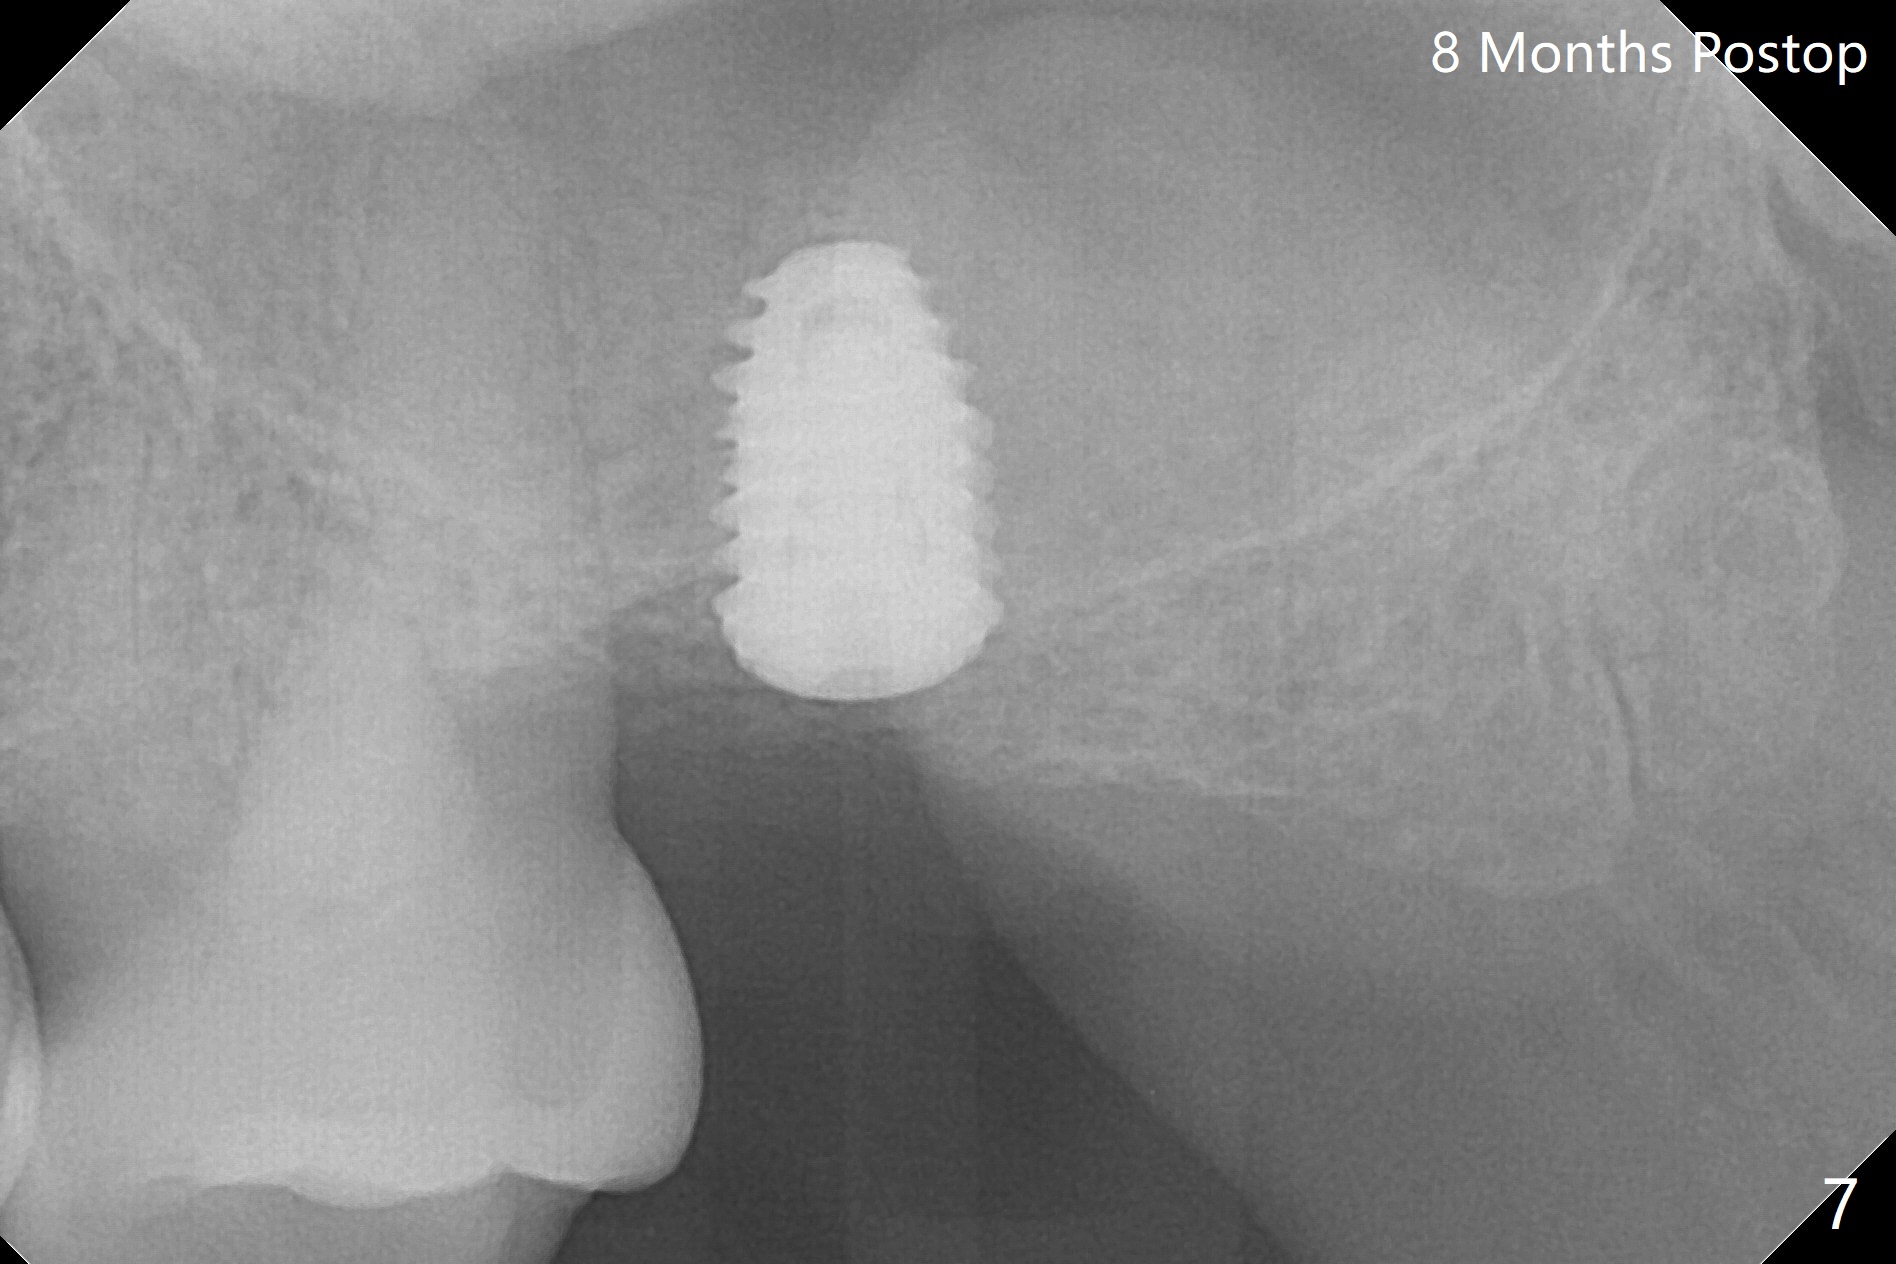

After 4.5x7.3 mm drill with 3 O-rings at #15, use 2.2x7.3 mm one with 2 O-rings. The sinus floor feels like to be perforated, but perio probe does not find the perforation. Nose blowing does not reveal air leakage. It seems fine when 3.0x7.3 mm one with 2 O-rings is being used. The sinus membrane perforates when Magic Sinus Lifter is used. Mixture of autogenous bone (from drills) and allograft does not stick to the periosteal elevator (Fig.1). Forty-minute centrifuge leads to separation of serum (Fig.2 S) from Red Blood Cell layer (R). The separation of the top tube is incomplete with RBC invade the serum layer in a few second (Fig.3 arrow). While the serum layer of the bottom tube is prepared for PRF membrane, a part of the serum layer of the top tube is withdrawn to make sticky bone (Fig.4). The top tube returns to the centrifuge for another 30 minutes to make the second PRF membrane. The first PRF membrane is inserted into the osteotomy and pushed into the sinus with empty feeling, followed by the sticky bone and last by the 2nd PRF membrane. A 5x7.3 mm implant is placed with ~ 10 Ncm, followed by a 6.8x4 mm healing abutment (Fig.5,6 (retrospectively healing screw should be used to reduce sinus-oral communication)). There is no mushroom in the sinus, but hopefully the sticky bone will stick to the bottom of the sinus for maturation. Sinus surgery precaution is provided. Next time tap or dummy implant will be used for sinus lift after initial osteotomy with guide. In fact the patient with diabetes under control has mild cold. The procedure should have been canceled. There is no postop nasal hemorrhage or discharge. The patient returns nearly 8 months postop. The wound is infected. The healing abutment is changed to a healing screw with oral antibiotic. Two weeks later, the area remains infected with symptoms (Fig.7-9). The healing screw is not covered completely. After implant removal, the sinus membrane is perforated. A piece of collagen plug (preferably Osteogen plug) is inserted (Fig.10,11). Because of the concavity, bone graft seems necessary when the wound heals. One week later, perimplantitis develops at #2. The patient is ready for the 3rd placement 1 year 5 months post last implant removal (Fig.12). The bone is 1.8 mm thick, apparently composing of 2 fused cortical plates. Make an incision for both external and internal sinus lift with retraction. Find the old guide to start osteotomy including bone trimmers and use Magic Lifter. If the membrane is broken, open the lateral window to repair with PRF.